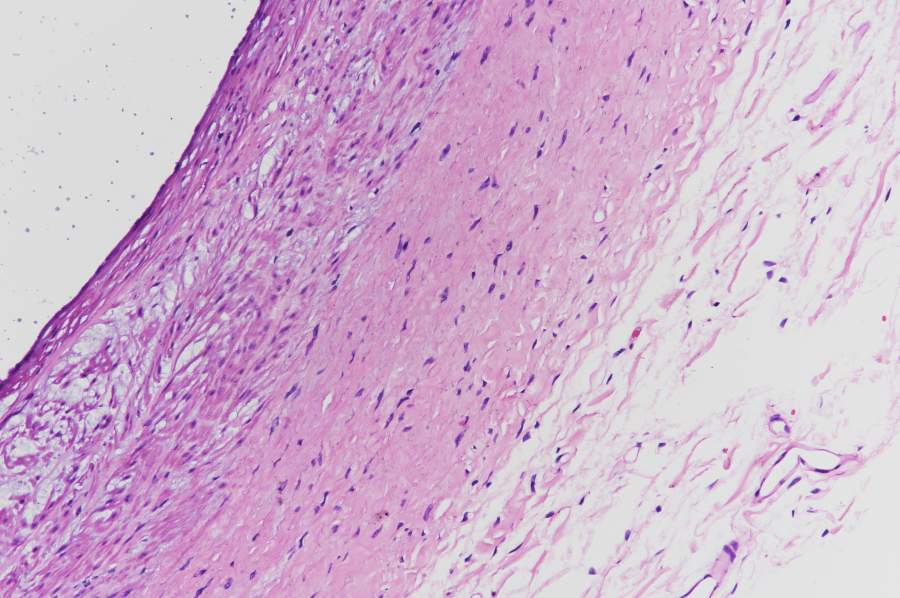

[求助] 求帮忙画出弹性内膜和弹性外膜的位置

该血管为猪的心脏血管。各位大侠能不能帮忙在图中分别标出弹性内外膜的位置,小生感激不尽,把不多的金币拿出来,略表心意